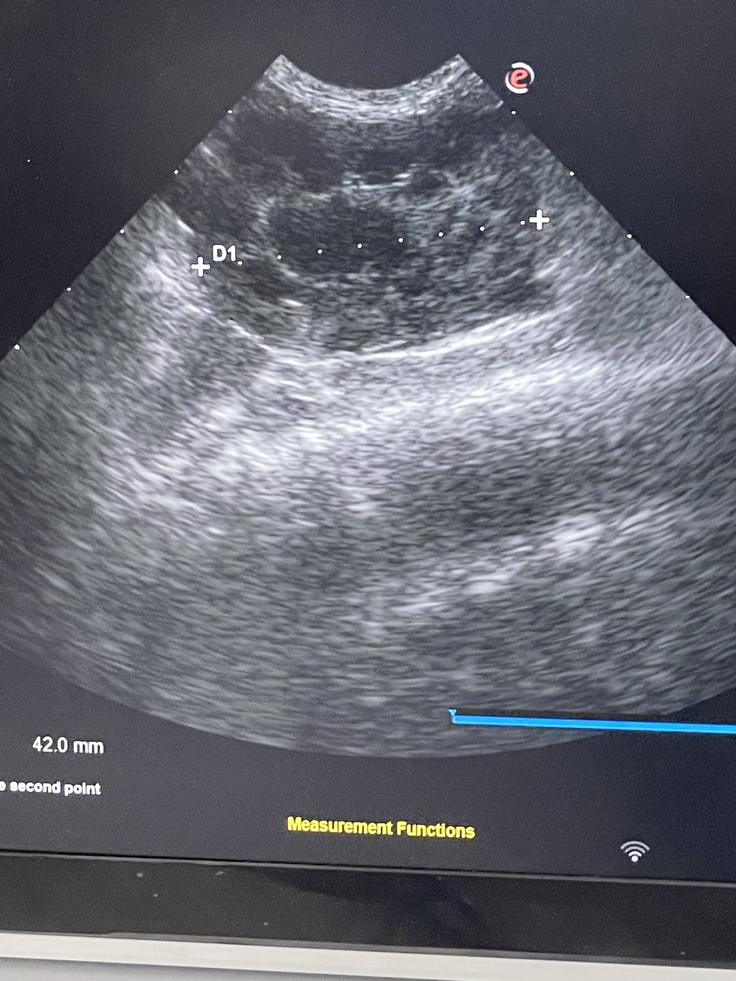

血液検査結果、エコー検査結果、ぶどう膜が出ている事、高熱が下がらない。などの要因からFIP(猫伝染性腹膜炎)ドライタイプと決定の診断を受けました。

(エコーにて ドライタイプと判明)